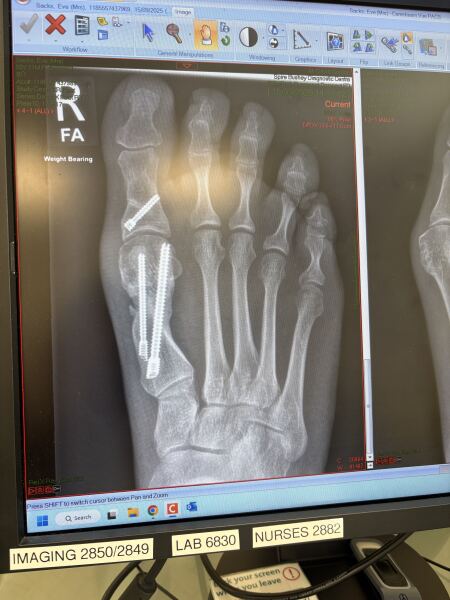

MeridaBrave · 04/10/2025 12:18

Fibrous · 04/10/2025 11:49

Really interesting to see the X-ray. Do you happen to have a before pic?

This is the before.

How the hell to cope with bunions?!